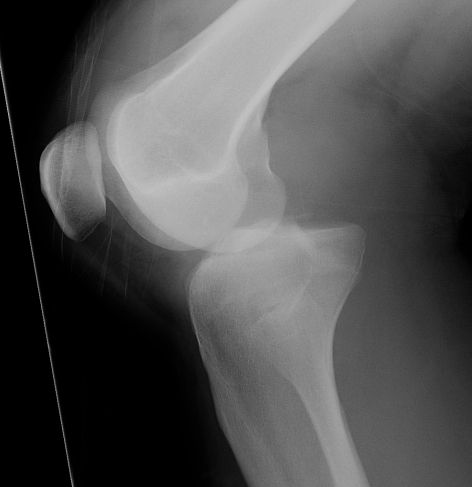

Fibula head avulsion / dislocation

Will typically have LCL and biceps femoris ligament attached

Fibular head avulsion

Fibula head avulsion and medial tibial plateau fracture